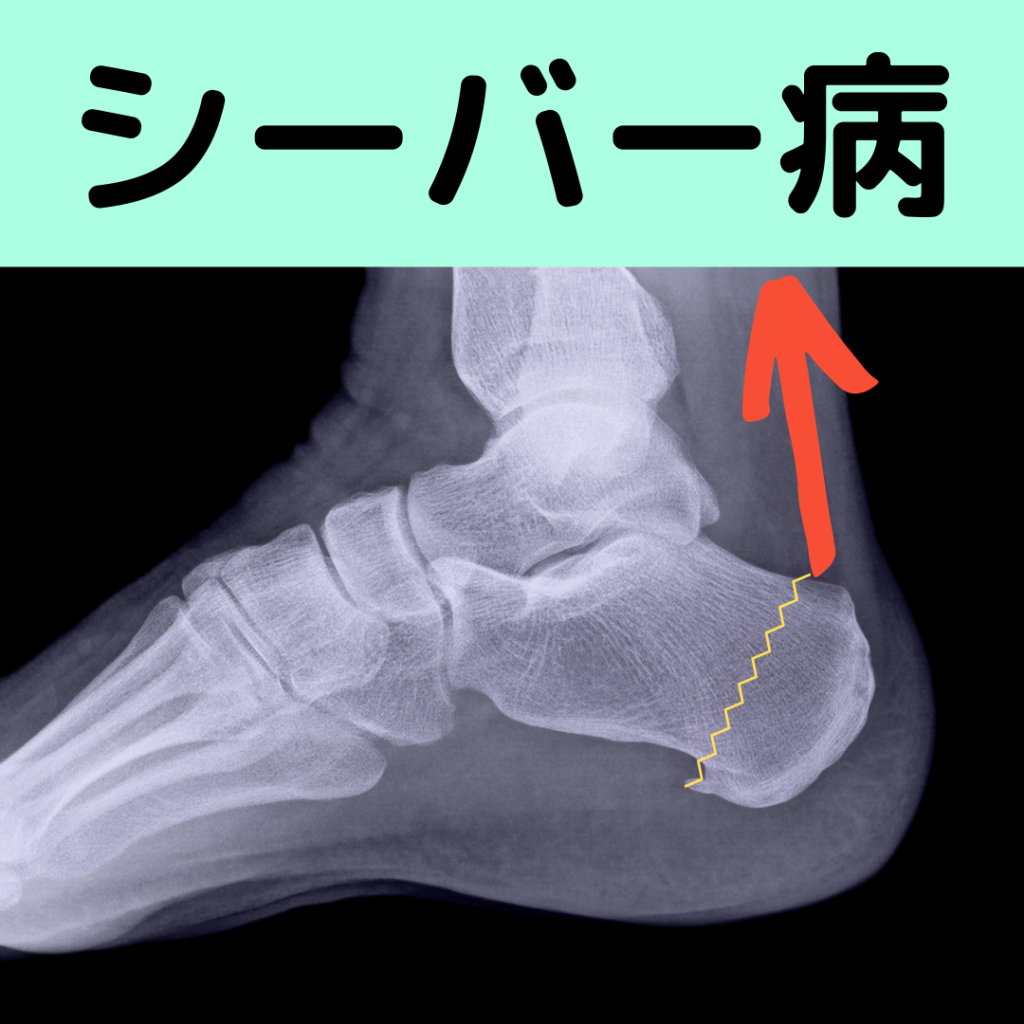

シーバー病はアキレス腱に引っ張られてかかとの骨端線からポキッと折れてしまう病気です。

シーバー病はかかとの骨ですが、すねの骨や太ももの骨にも骨端線があります。この部分は構造的にその他の部分と比べて弱く、強い力がかかると容易に折れてしまいます。(写真はひざの骨)